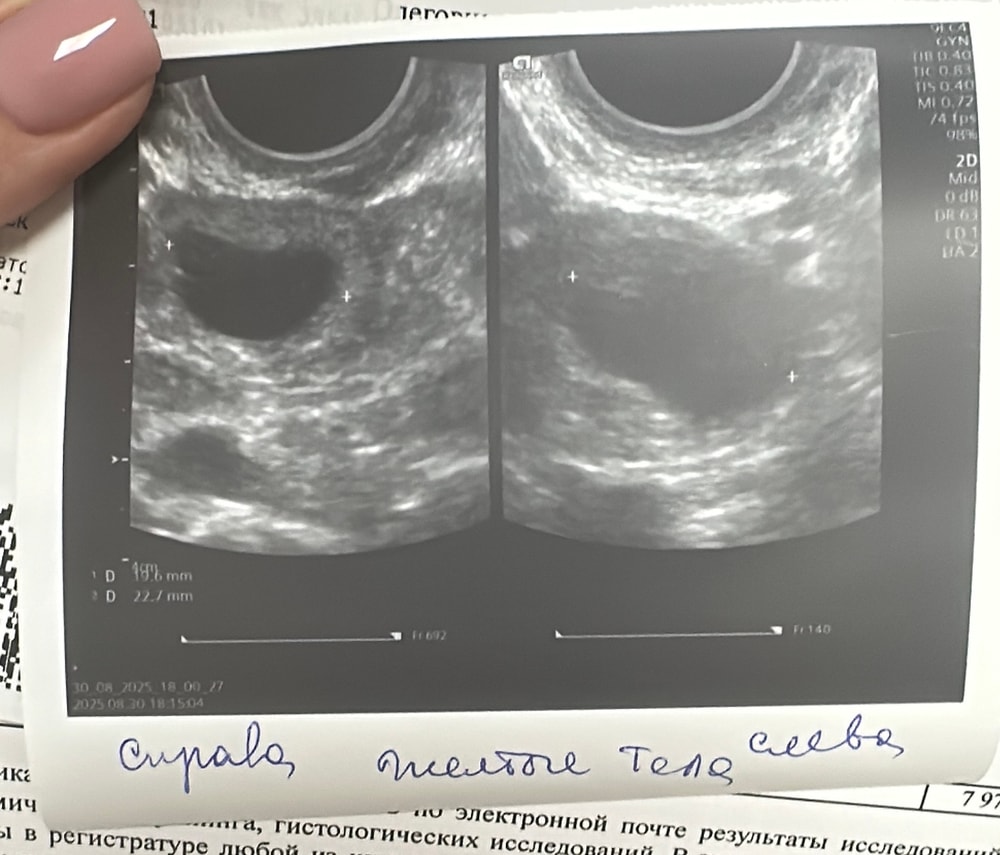

Имеем на 8- 9 -10 дц подтвержденную узи двойную овуляцию ( впервые увидела у себя такое чудо ) . Ранняя при цикле 24-26 дней . Эндометрий 9 мм был на момент 11 дц .

У меня частенько 2 жт, одно с нового цикла, а другое не рассасывается почему то с прошлого 🤷♀️